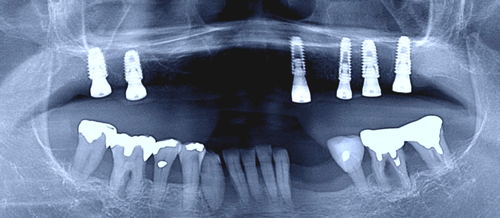

CT画像の分析を徹底的にした結果、僅かに残された骨の厚みと高さのある部分に、6本のインプラントを移植することが出来ました。

長時間の施術、お疲れさまでした。アゴの骨幅が薄く、高さも無い場所に、歯肉をメスで切らずにインプラントを移植するのは相当ハードでしたが、僅かに骨のありそうな場所にインプラント移植を行いました。総て骨とガッチリ固定してくれることを願っています。また、スタッフのみんなも一年間本当にありがとう!